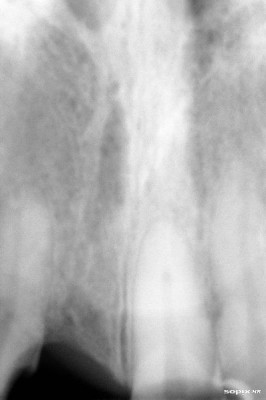

Radiografía inicial